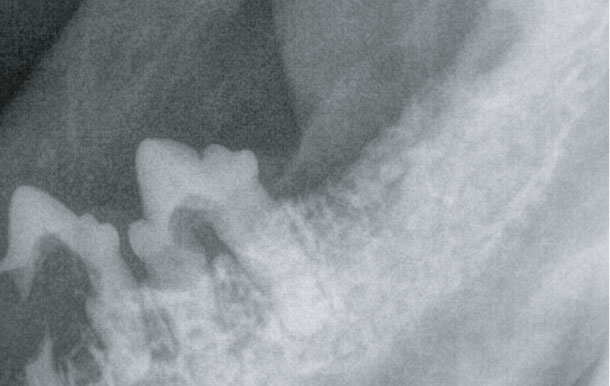

고양이 치아 흡수성 병변 (FORL)

고양이의 구강 질환 중 가장 일반적이며 통증이 심한 질환입니다.

치아의 에나멜질과 심부의 상아질에 미란이 일어납니다.

육안적으로 확인되는 경우도 있으나, 정확한 평가를 위해서는 치과 방사선을 촬영해 봐야합니다.

병변이 관찰될 경우, 영향을 받은 치아 뿐만 아니라 전체 치아를 발치해야 하기 때문에

정확한 진단과 치료가 필요합니다.